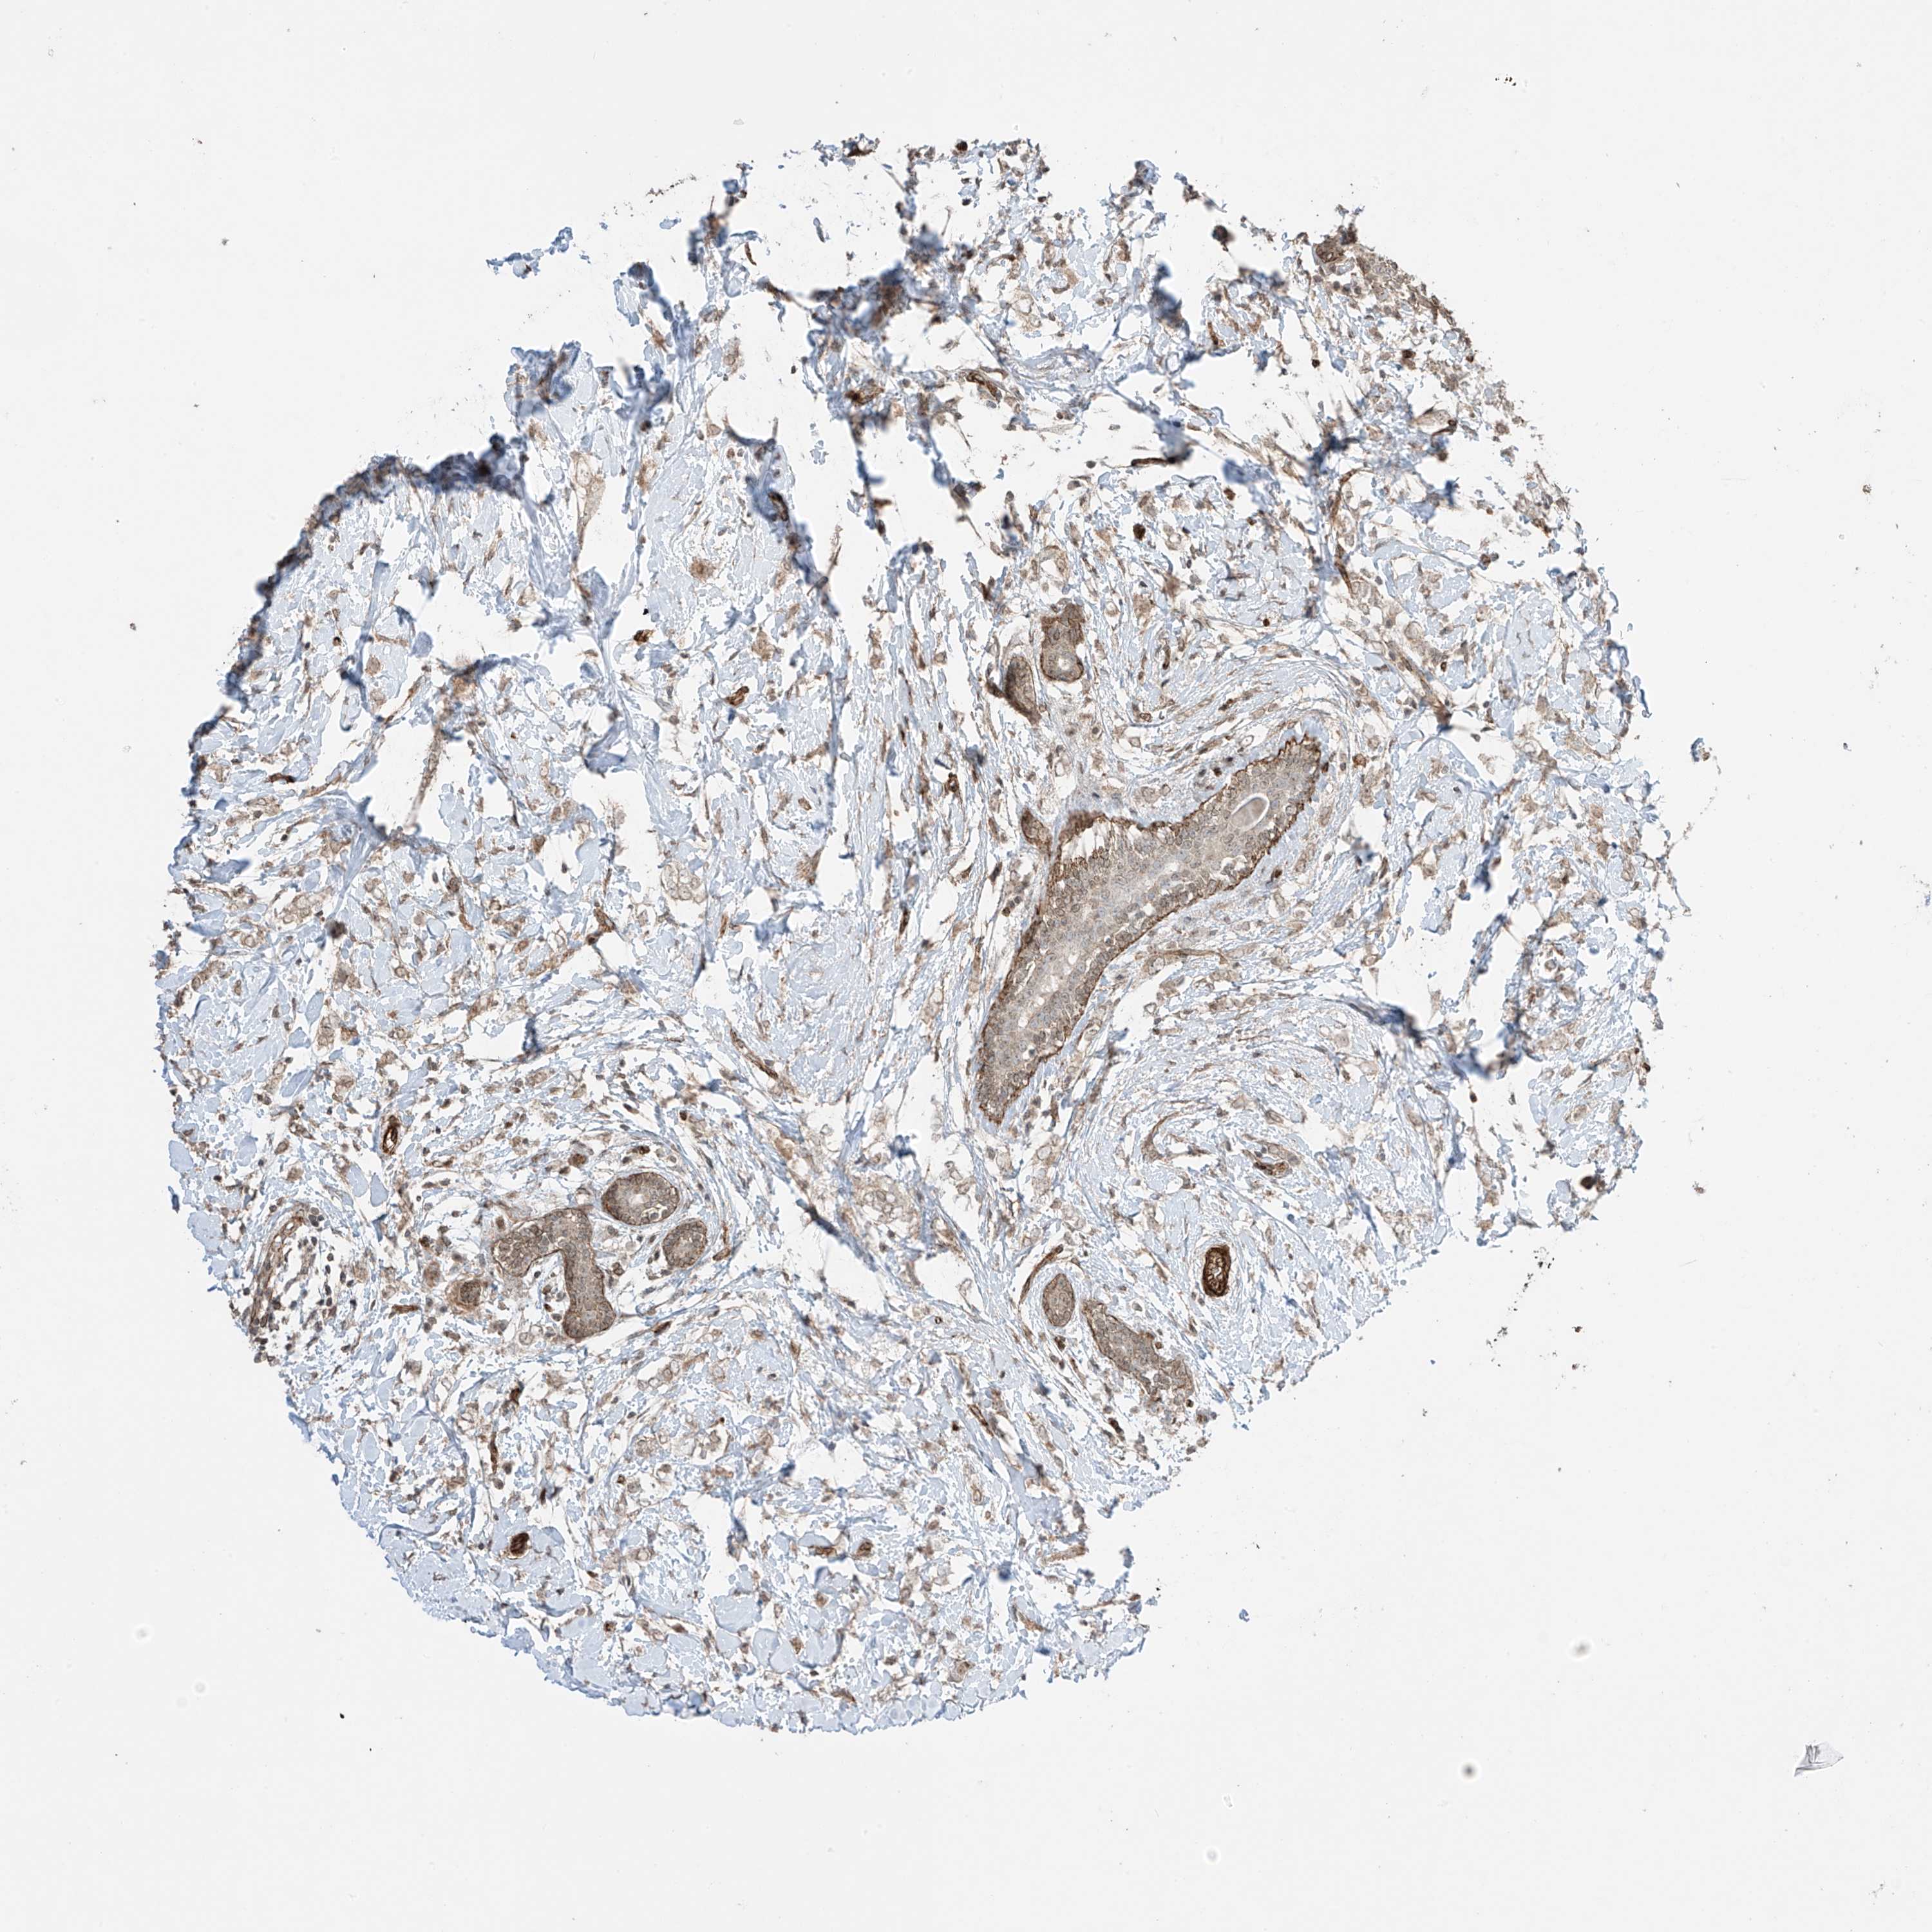

CANCER BREAST CANCER Show tissue menu

BRCA TCGA BRCA VALIDATION PROTEIN EXPRESSION